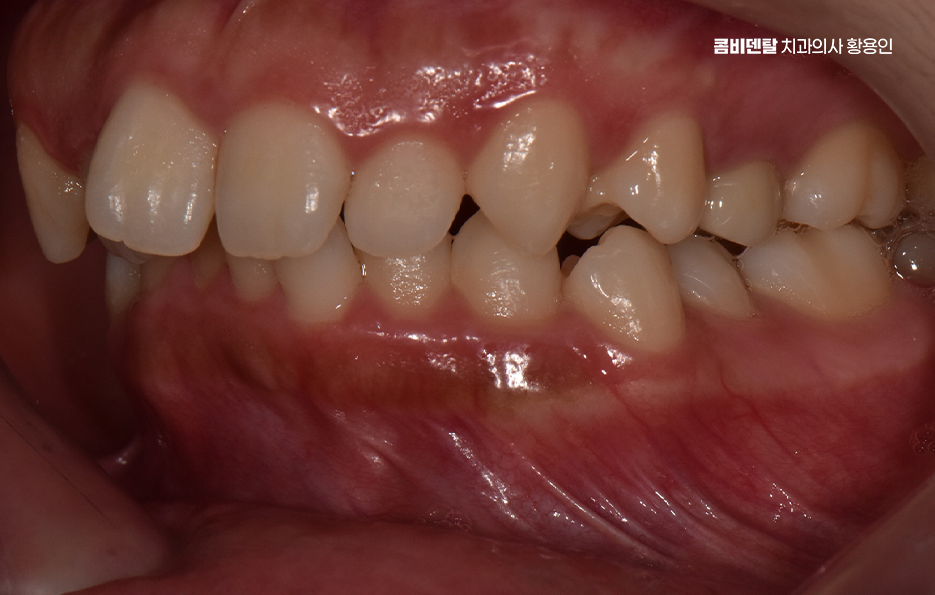

돌출입이라는 표현은 단순히 입이 튀어나와 보인다는 인상만을 의미하지는 않으며 치아가 앞으로 기울어져 있거나, 잇몸뼈 자체가 앞으로 나와 있거나, 입술 두께와 근육 사용 습관까지 복합적으로 작용해 나타나는 경우가 많아서 겉으로 보기에는 비슷한 돌출입처럼 보여도, 실제 교정 계획은 사람마다 크게 달라질 수 있었어요.

턱뼈의 위치와 형태도 중요한 기준이 되며 잇몸뼈 자체가 과도하게 앞으로 튀어나와 있는 골격성 돌출입의 경우에는 비발치 교정만으로는 한계가 있는 경우가 많은 반면 턱뼈의 위치는 비교적 정상 범위에 있고, 치아 배열로 인해 돌출이 강조되어 보이는 경우라면 비발치 교정이 현실적인 선택지가 될 수 있었어요.

하지만 비발치 돌출입 교정에는 분명한 한계점도 있는데 우선 돌출입이 심한 경우에는 돌출 개선 효과의 한계로 발치 교정에 비해 치아를 뒤로 이동시킬 수 있는 양이 제한적이기 때문에, 돌출이 심한 경우에는 기대했던 만큼의 변화가 나타나지 않을 수 있어요.

따라서 돌출입 비발치 교정을 고려할 때 중요한 것은 나에게 어떤 방식이 적합한지를 잘 따지는 것이며 기술적으로 비발치가 가능하다고 해서, 그 방법이 가장 좋은 선택이라는 의미는 아닐 수 있으며 현재 치아 상태, 얼굴 인상 변화에 대한 기대, 잇몸 건강, 장기적인 안정성까지 함께 고려해서 치료 계획을 세워야 하기 때문에 경험 많은 교정 전문의와 먼저 충분히 상의하고 판단하실 필요가 있었어요